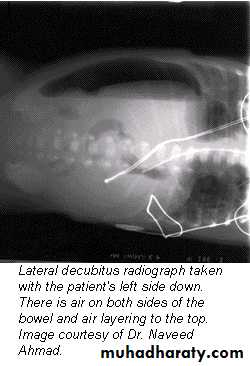

• Lateral decubitus

The main purpose of horizontal beam films is to detect air-fluid levels and free intraperitoneal air

Pneumoperitoneum

Defined as free gas in the peritoneal cavityThe commonest cause is perforated peptic ulcer and two-thirds of such cases are recognizable radiologically

Pneumoperitoneum under the right hemidiaphragm is usually easy to recognize, but free gas under the left hemidiaphragm is difficult to recognize because of the overlapping gas shadows of the stomach and splenic flexure.

Gas under the diaphragm is much easier to diagnose on an erect chest film than on an upright abdominal film